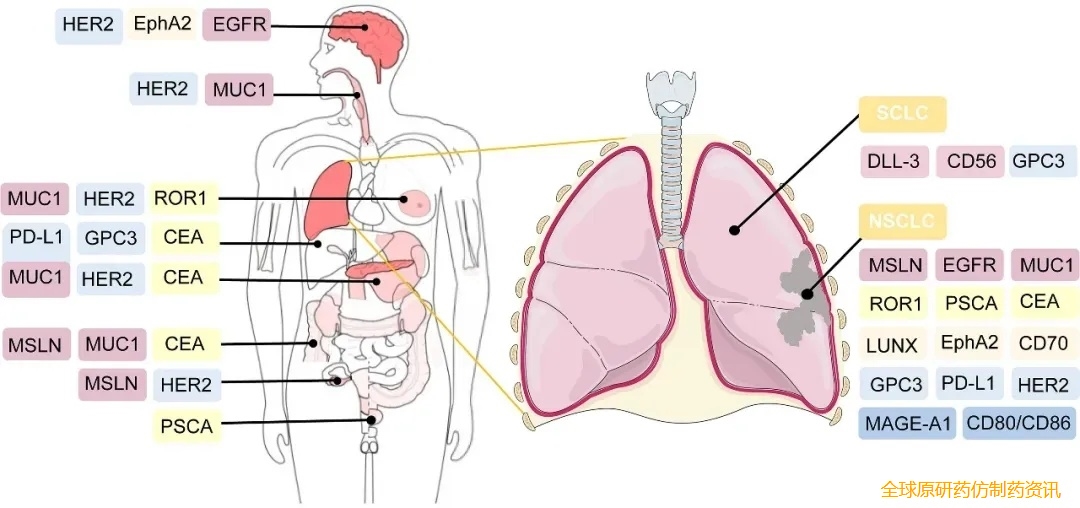

好消息是,目前有多款CAR-T临床实验正在火热招募中,主要针对Claudin18.2、GPC3、GUCY2C、PSMA、CEA、间皮素(mesothelin)、MUC-1、BCMA、CD1、CD20等靶点。以及胰腺癌、胃癌、肝癌、结直肠癌、神经胶质瘤、肺癌、多发性骨髓瘤、多发性骨髓瘤、弥漫大B细胞淋巴瘤等癌种。

▼CAR-T细胞疗法的潜在治疗靶点